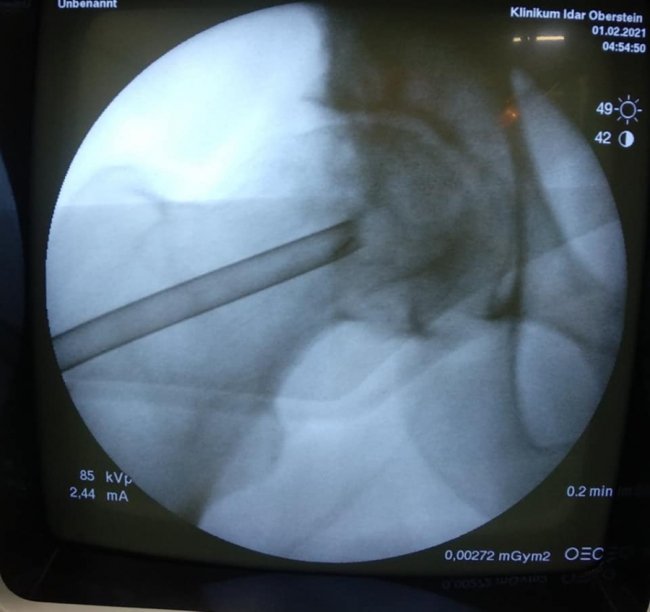

В ході подальшого дослідження в головці правої стегнової кістки виявили кисту розмірами 2*2*2,5 см.

"В ході клінічного розбору було прийняте рішення на користь органозберігаючої операції. Куратор напрямку пухлин та пухлиноподібних захворювань Шевчик Я.В. виконав унікальну операцію: декомпресійну пластику кисти головки стегнової кістки", - йдеться в дописі.

Ця операція полягає у видаленні вмісту кисти, очищенні її стінок та виповнення дефекту кістковим трансплантатом з доступу розміром 3 см.